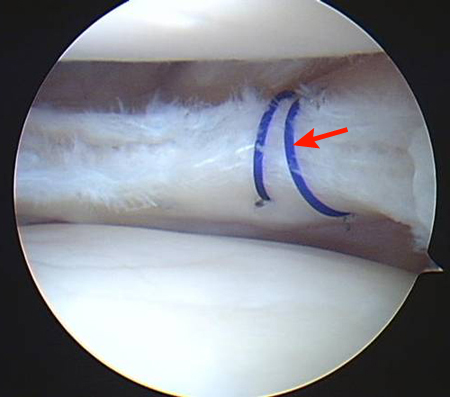

Ⅲ度以上的半月板损伤需要手术,但手术不等于切除,在切除半月板之前先考虑半月板缝合。

随着医学的发展进步,针对各种半月板损伤的缝合技术在不断完善,如今大部分红区的半月板损伤都能够缝合,加上红区血运好,在缝合之后的愈合率也比较高。患者在诊断出半月板损伤后,对于轻度损伤做好保守治疗并定期复诊,对于重度损伤及时选择关节镜下缝合修复,并非一定要切除半月板。